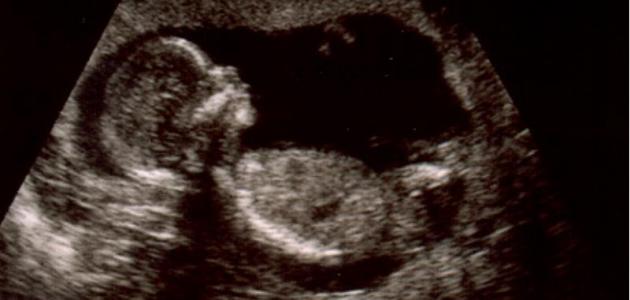

لقد مكننا التصوير فوق الموجات الصوتيّة القدرة على رؤيّة حركات الجنين، فسيبدأ طفلك بالحركة قبل إحساسك بذلك، وستتغيّر حركاته كلّما نما وتطوّر، وإذا كنت محظوظة سيكون طفلك مستيقظاً عند جلسة التصوير وستتمكنين من رؤية حركاته، لكن ما هي هذه الحركات التّي يقوم بها؟: